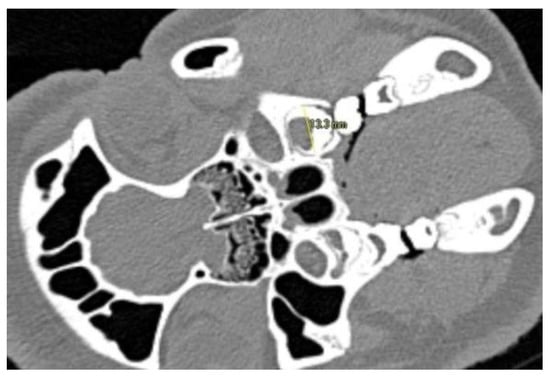

| Sectional Plane | Measurement Axis | Anatomical Orientation |

|---|---|---|

| Axial | coronal-apical | Parallel with nasal septum and central through tooth |

| buccal-oral | Parallel with palatal vault and at the level of the alveolar margin | |

| Coronal | mesial-distal | Central at the level of the alveolar ridge and central through the tooth |

| buccal-oral | Orthogonal with palatine suture and central through tooth | |

| Sagittal | mesial-distal | Central through pulp cavity |

| coronal-apical | Orthogonal with alveolar ridge and central through tooth |